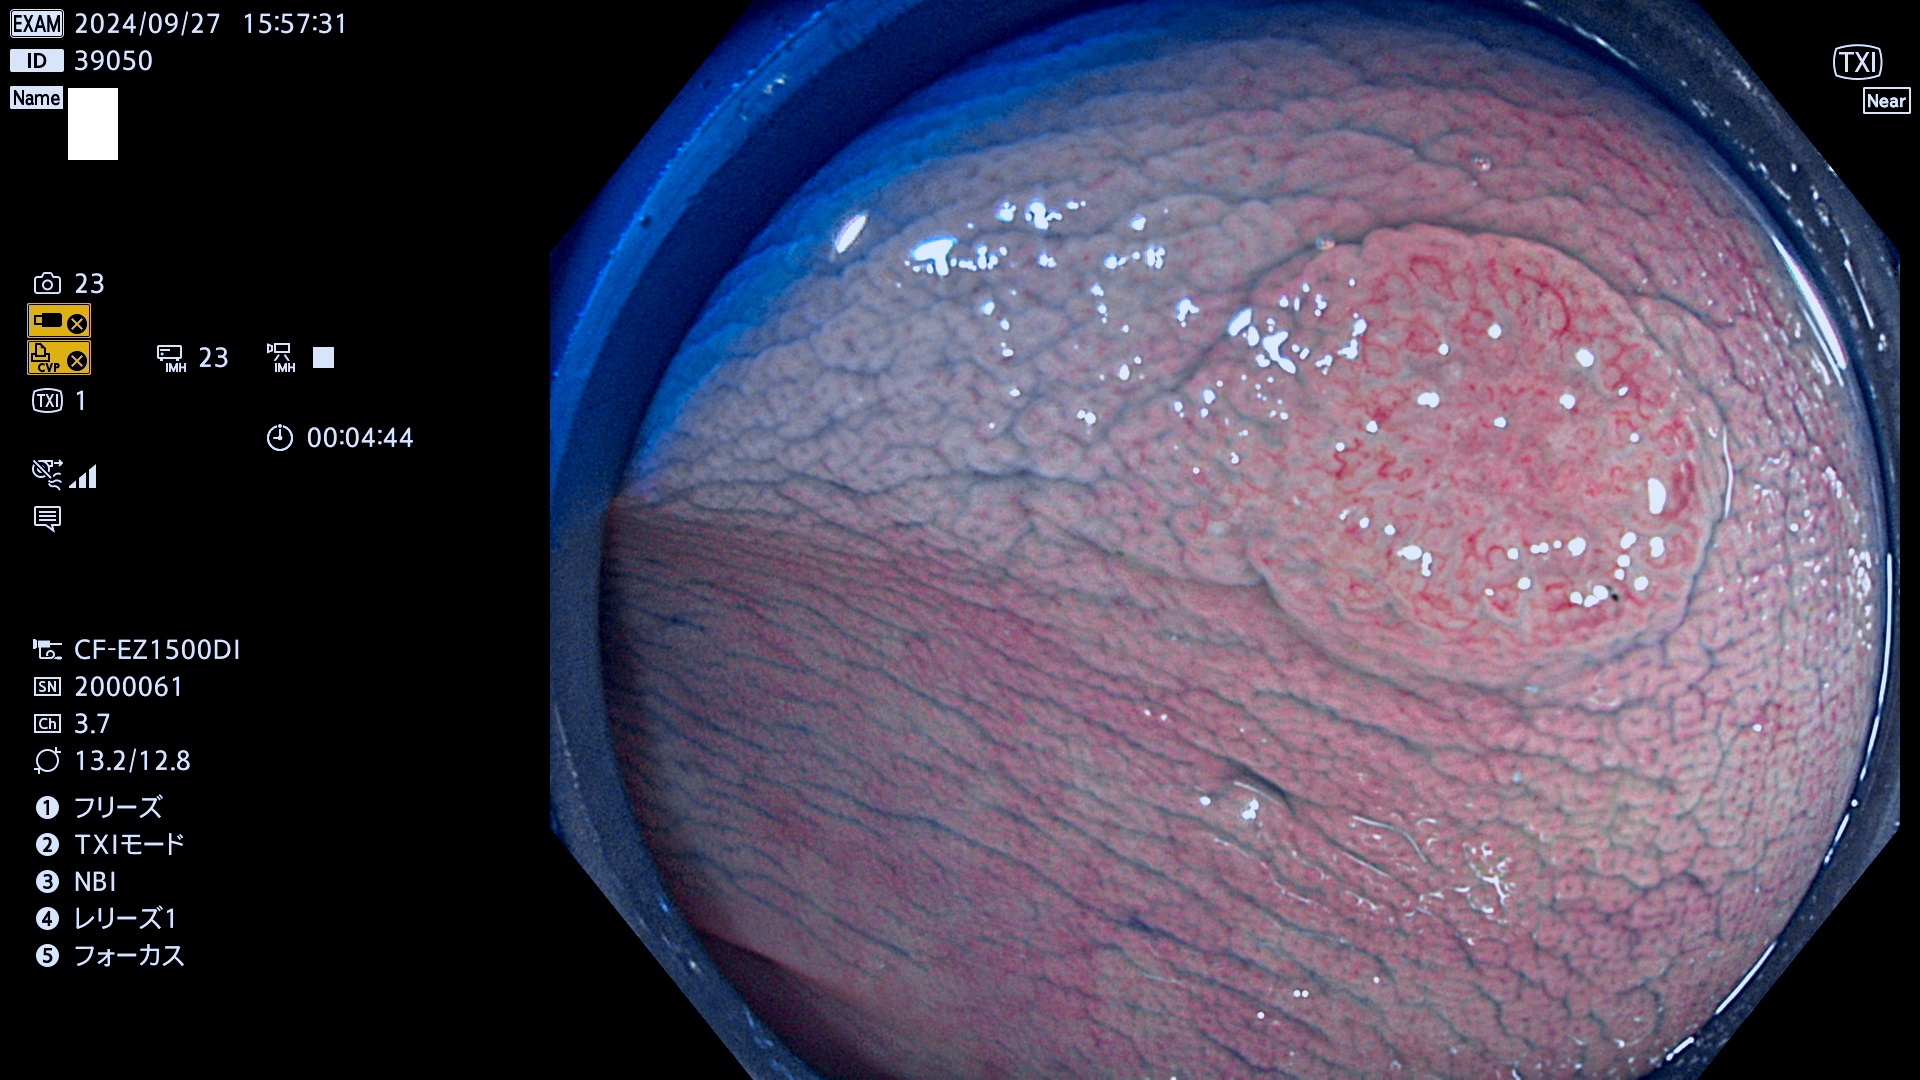

今週のUb、Uc型腺腫

完全に平坦な物をUb、陥凹している物をUcと呼びます。最も発見が難しく危険な病変です。

毎週の検査(木・金・土・日)に発見されたUb、Uc型・腺腫を、その週の日曜の夜にUPし1週間、提示します。

抽出の対象期間 2024年9月26日〜9月29日の4日間(48件の検査)12件 (12/48=25%)